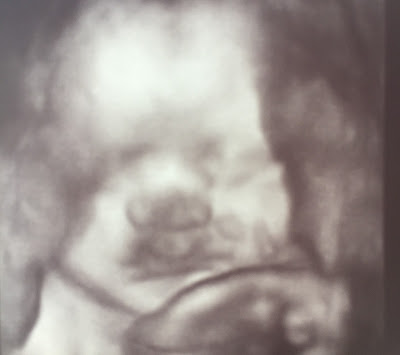

Apparently my belly is measuring 3.5 weeks ahead of schedule (yikes!). So Dr. Bonilla sent me for an ultrasound today to see how much Rocco was weighing. As you can imagine, my vagina was trembling. It wouldn't necessarily change the due date, but depending on the baby's size, we may have to consider a C-section. Off we went to the sonogram office and happy to report that Rocco is measuring accordingly. He's at 3lbs and 13oz- growing big and strong! The amazing technician, Monica, spent a generous amount of time letting us 'oooh and aaaah' at Rocco and we were FINALLY able to get a good shot of his delicious little face (see below)! He was already in position so all those kicks and jabs I'm feeling are thanks to his legs and little arms! He even smiled in a few of the shots. He's got a little bit of hair, based on the fuzz around his head. His heartbeat was at 131, which is great and all his measurements, his organs, his spine, were all looking good! I'm a very happy mommy and so is my vagina- for now! Rocco looks so much like Maya and my baby cousin, Alexander, even Coco couldn't deny the instant resemblance. Poor Coco. His genes are no match for mine! As long as he's got the Buccio lips, I'm complete!

| Hello baby! Rocco Sebastian Buccio at 30 weeks and 2 days. Is that a smile I see?! |